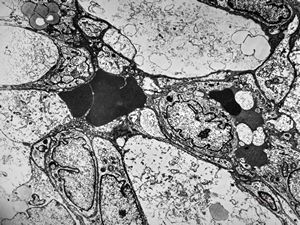

F,49y. | purulent meningitis- meningococcal v.s.